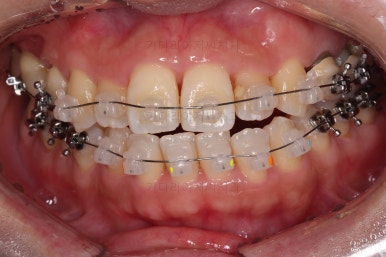

환자분이 선택하신 장치는 데이몬 클리어라고 하는 자가결찰 세라믹 장치입니다.

자가결찰 세라믹 중에 가장 심미적으로 우수한 장치가 데이몬 클리어인데요.

철사를 제외한 모든 파트가 세라믹으로 되어있습니다.

장치를 부착한 모습 참고해 주시고요.

아랫니는 중앙선을 맞추기 위해서 미니스크류를 이용해 한 쪽으로 당기는 중이고요.

이 과정에서 아랫니들이 약간은 뒤로 들어가져서 아랫입술 부위의 돌출감을 아주 약간은 줄일 수 있습니다.

윗니 임플란트 할 자리는 적절히 계속 맞춰줍니다.

중앙선도 점점 맞아지고 있어요.